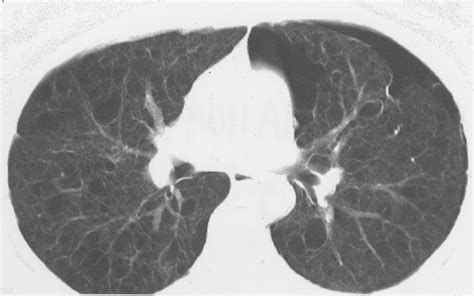

A Spiral CT Scan, also known as a helical CT scan, is a type of computed tomography that uses X-rays to create detailed images of the body. Unlike traditional CT scans, which capture images in a step-by-step manner, a Spiral CT Scan continuously rotates around the patient, capturing a spiral or helical path. This continuous movement allows for faster and more comprehensive imaging, reducing the time a patient spends in the scanner and minimizing motion artifacts.

One of the key advantages of a Spiral CT Scan is its ability to capture images in a continuous spiral, allowing for faster and more detailed imaging. This is particularly beneficial for imaging moving organs, such as the heart and lungs, where traditional CT scans might produce blurry or incomplete images.

• Cancer Detection: Spiral CT Scans are instrumental in detecting and staging cancer, particularly in the lungs, liver, and other organs. The detailed images help in identifying tumors and assessing their size and location.